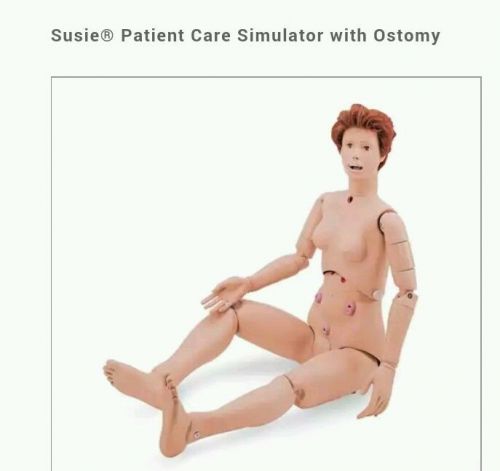

Susie Patient Care Simulator w/ Ostomy Mannequin Nursing CNA Training MSRP $976!